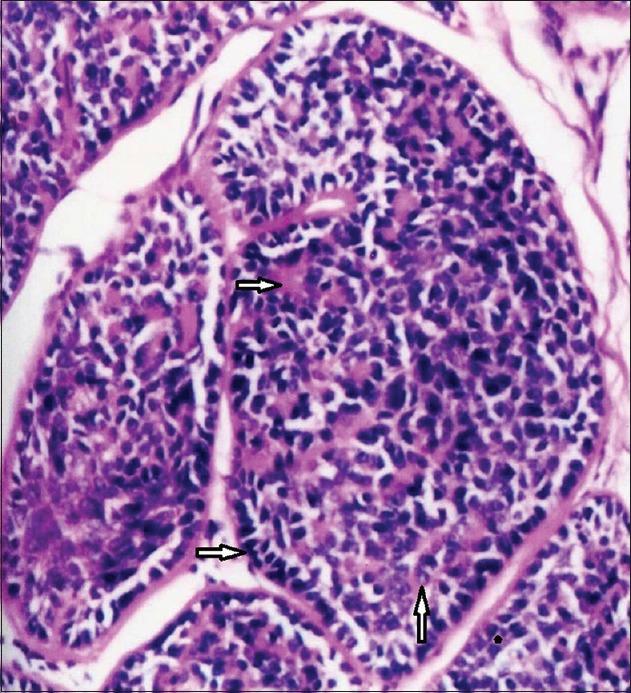

Soft pink nodules on the scalp.